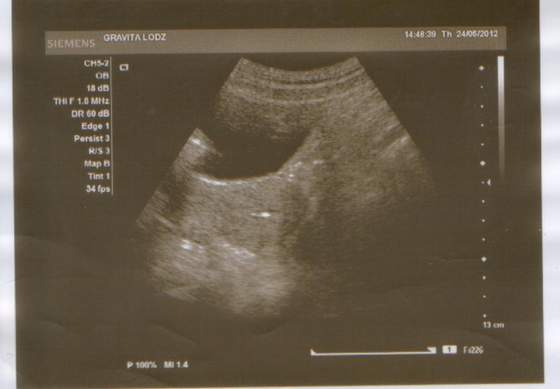

bez tytułu.jpg

A oto nasze maleństwo:) oby z nami zostało i rosło coraz większe i większe:)